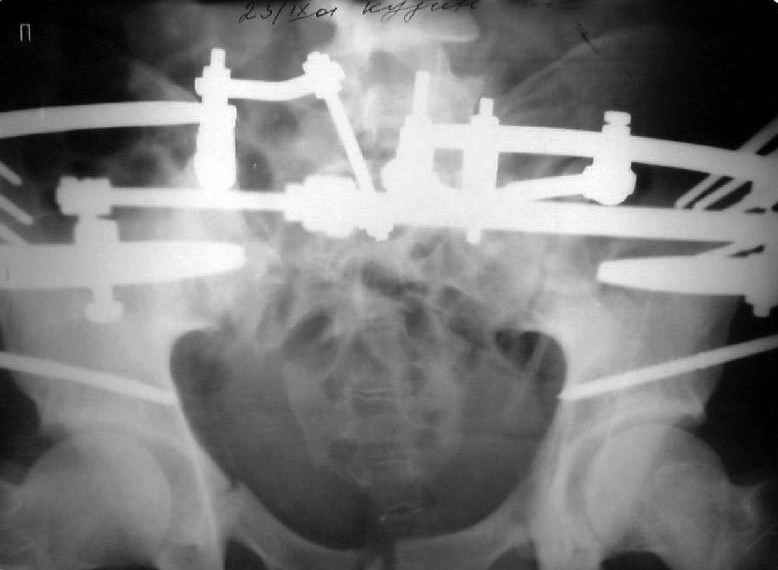

Re: Застарелый перелом таза

Для информации к размышлению о возможности исправления имеющейся деформации предлагаю похожий случай.